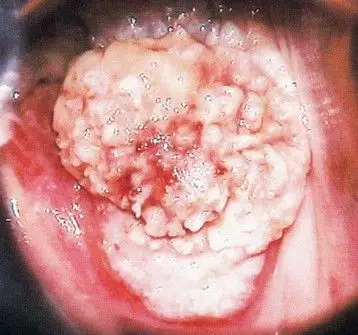

宫颈癌的发病率和死亡率居于第一位在中国女性生殖系统恶性肿瘤中排名

分期讨论宫颈癌的治疗

宫颈癌图片 (32)